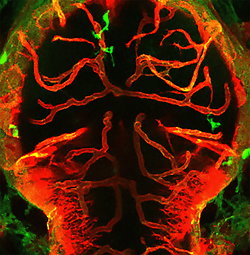

Untersuchung im Tiermodell: Hypertonie-bedingte Umprogrammierung von Immunzellen schädigt das Hirn27. Februar 2023 Studienleiterin Suphansa Sawamiphak vom Max Delbrück Center. Foto: ©Felix Petermann/MDC Bluthochdruck schädigt Herz, Gehirn und Blutgefäße. Eine wichtige Rolle spielt dabei das Immunsystem, wie eine Arbeitsgruppe vom Max Delbrück Center jüngst aufdeckte. Bei hypertonen Zebrafischen bewirken Entzündungen, dass Makrophagen und Mikroglia Blutgefäße nicht schützen, sondern sie angreifen. Entzündungsreaktionen im Körper tragen zum Bluthochdruck bei und ziehen Organe in Mitleidenschaft. „Herkömmliche Medikamente können zwar den Blutdruck senken, bei vielen Betroffenen erreicht man damit aber nicht die erhoffte Schutzwirkung für die Organe“, sagt Dr. Suphansa Sawamiphak, Leiterin der Arbeitsgruppe Kardiovaskulär-Hämatopoetische Interaktionen am Max Delbrück Center. Das werde im Gehirn besonders deutlich, wo bei Bluthochdruck feine Blutgefäße durchlässig werden oder absterben. „Demnach muss es im Gesamtgeschehen noch weitere Schaltstellen geben, die wir mit konventionellen Wirkstoffen nicht erreichen.“ Schon länger ist bekannt, dass Bestandteile des Immunsystems hier eine Rolle spielen könnten. Wie das im Detail abläuft, ist bislang nicht bekannt. Um den verantwortlichen biologischen Mechanismen auf den Grund zu gehen, untersuchte Sawamiphak zusammen mit ihrem Team am Max Delbrück Center und Kolleginnen und Kollegen aus Italien und der Schweiz Larven des Zebrafisches. „Das ist ein sehr gutes Modellsystem für viele Fragestellungen, weil wir die Tiere durch Veränderung der Umgebung leicht manipulieren können“, sagt die Biologin und erklärt weiter: „Weil junge Zebrafische durchsichtig sind, können wir die Auswirkungen am lebenden Tier beobachten.“ Immunzellen schädigen Blutgefäße im Zebrafisch-Gehirn Interaktionen zwischen Makrophagen/Mikroglia (grün) und Hirngefäßen (rot) führen zu Gefäßrückbildung und Zelltod im Gehirn von Zebrafischen. Bild: ©Maria P. Kotini/Universität Basel Um die Rolle des Immunsystems bei Bluthochdruck zu analysieren, haben die Forschenden Zebrafischlarven im Wasser mit niedriger Ionenkonzentration aufgezogen. Dadurch entsteht bei den Tieren ein Ionenungleichgewicht im Körper, das vergleichbar ist mit übermäßigem Salzkonsum beim Menschen und das zu Bluthochdruck führt. Anschließend haben sie untersucht, welche Auswirkungen dies auf die Blutgefäße im Gehirn hat. Ihre Forschungsergebnisse publizierten sie im Fachjournal „Cardiovascular Research“. Nach den Beobachtungen der Forschenden führt Bluthochdruck zu mehr Makrophagen und Mikroglia, die mit dem Endothel in Kontakt treten und die Gefäßwände zunehmend schwächen. Auch die Blut-Hirn-Schranke, die das Gehirn vor schädlichen Substanzen und Krankheitserregern schützt, nimmt Schaden. „Das Interessante ist, dass Makrophagen und Mikroglia bei gesundem Blutdruck normalerweise die Gefäße schützen“, sagt Sawamiphak. „Unsere Ergebnisse deuten darauf hin, dass Makrophagen beziehungsweise Mikroglia bei Bluthochdruck regelrecht umprogrammiert werden.“ Keine Organschäden bei Blockade von Interferon-Gamma Eine wichtige Rolle dabei spielen den Untersuchungen zufolge Entzündungsbotenstoffe wie Interferon(IFN)-Gamma, die unter Bluthochdruckbedingungen vermehrt ausgeschüttet werden. Um diesen Zusammenhang experimentell zu untermauern, schalteten die Wissenschaftlerinnen und Wissenschaftler das Gen für den IFN-Gamma-Rezeptor-1 aus, an den IFN-Gamma normalerweise bindet. Bei diesen Fischen hinterließ der Bluthochdruck keine Schäden in Blutgefäßen und Blut-Hirn-Schranke. Mitverantwortlich scheint der BMP-5-Signlaweg zu sein. Im Rahmen eines transkriptomischen Ansatzes identifizierte Sawamiphaks Team BMP-5 als herunterreguliertes Gen in mit Ionenmangel behandelten Makrophagen/Mikroglia, welches durch IFN-Gamma-Blockade wiederhergestellt werden konnte. Eine Supplementierung von BMP-5 milderte den zerebralen Mikrogefäßverlust im hypertonen Zebrafischmodell ab. Auch bei Mäusen gelang dem Team der Nachweis, dass Wirkstoffe, die IFN-Gamma hemmen, typische Begleiterscheinungen von Bluthochdruck – darunter Schäden der Blut-Hirn-Schranke, Abbau der Blutgefäße im Gehirn sowie kognitive Defizite – verhindern können. „Unsere Ergebnisse eröffnen eine völlig neue Perspektive auf die Rolle von Entzündungsvorgängen bei der Entstehung von Bluthochdruck“, unterstreicht Sawamiphak die Bedeutung ihrer Arbeit. Nun gelte es, die beteiligten Immunzellen und Immunmodulatoren genauer zu charakterisieren und ihre Rolle bei höheren Tieren bis hin zum Menschen zu überprüfen. Sollte sich dies bestätigen, hätte das Team mit dieser Studie neue Angriffspunkte für die Therapie bei Bluthochdruck gefunden. Davon würden insbesondere Betroffene profitieren, bei denen herkömmliche Wirkstoffe nicht vor zunehmenden Organschäden zu schützen vermögen.